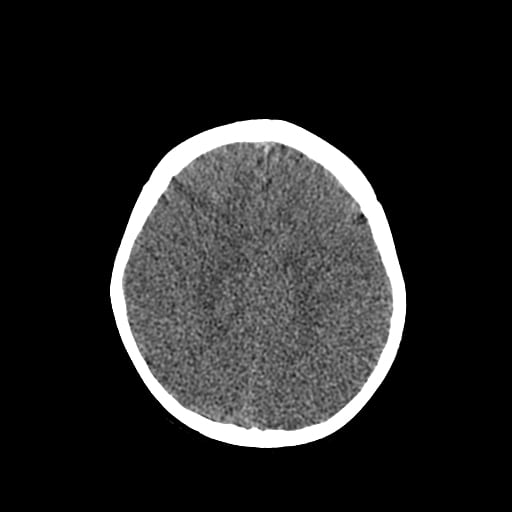

Age: 1

Sex: Male

Indication: Fall